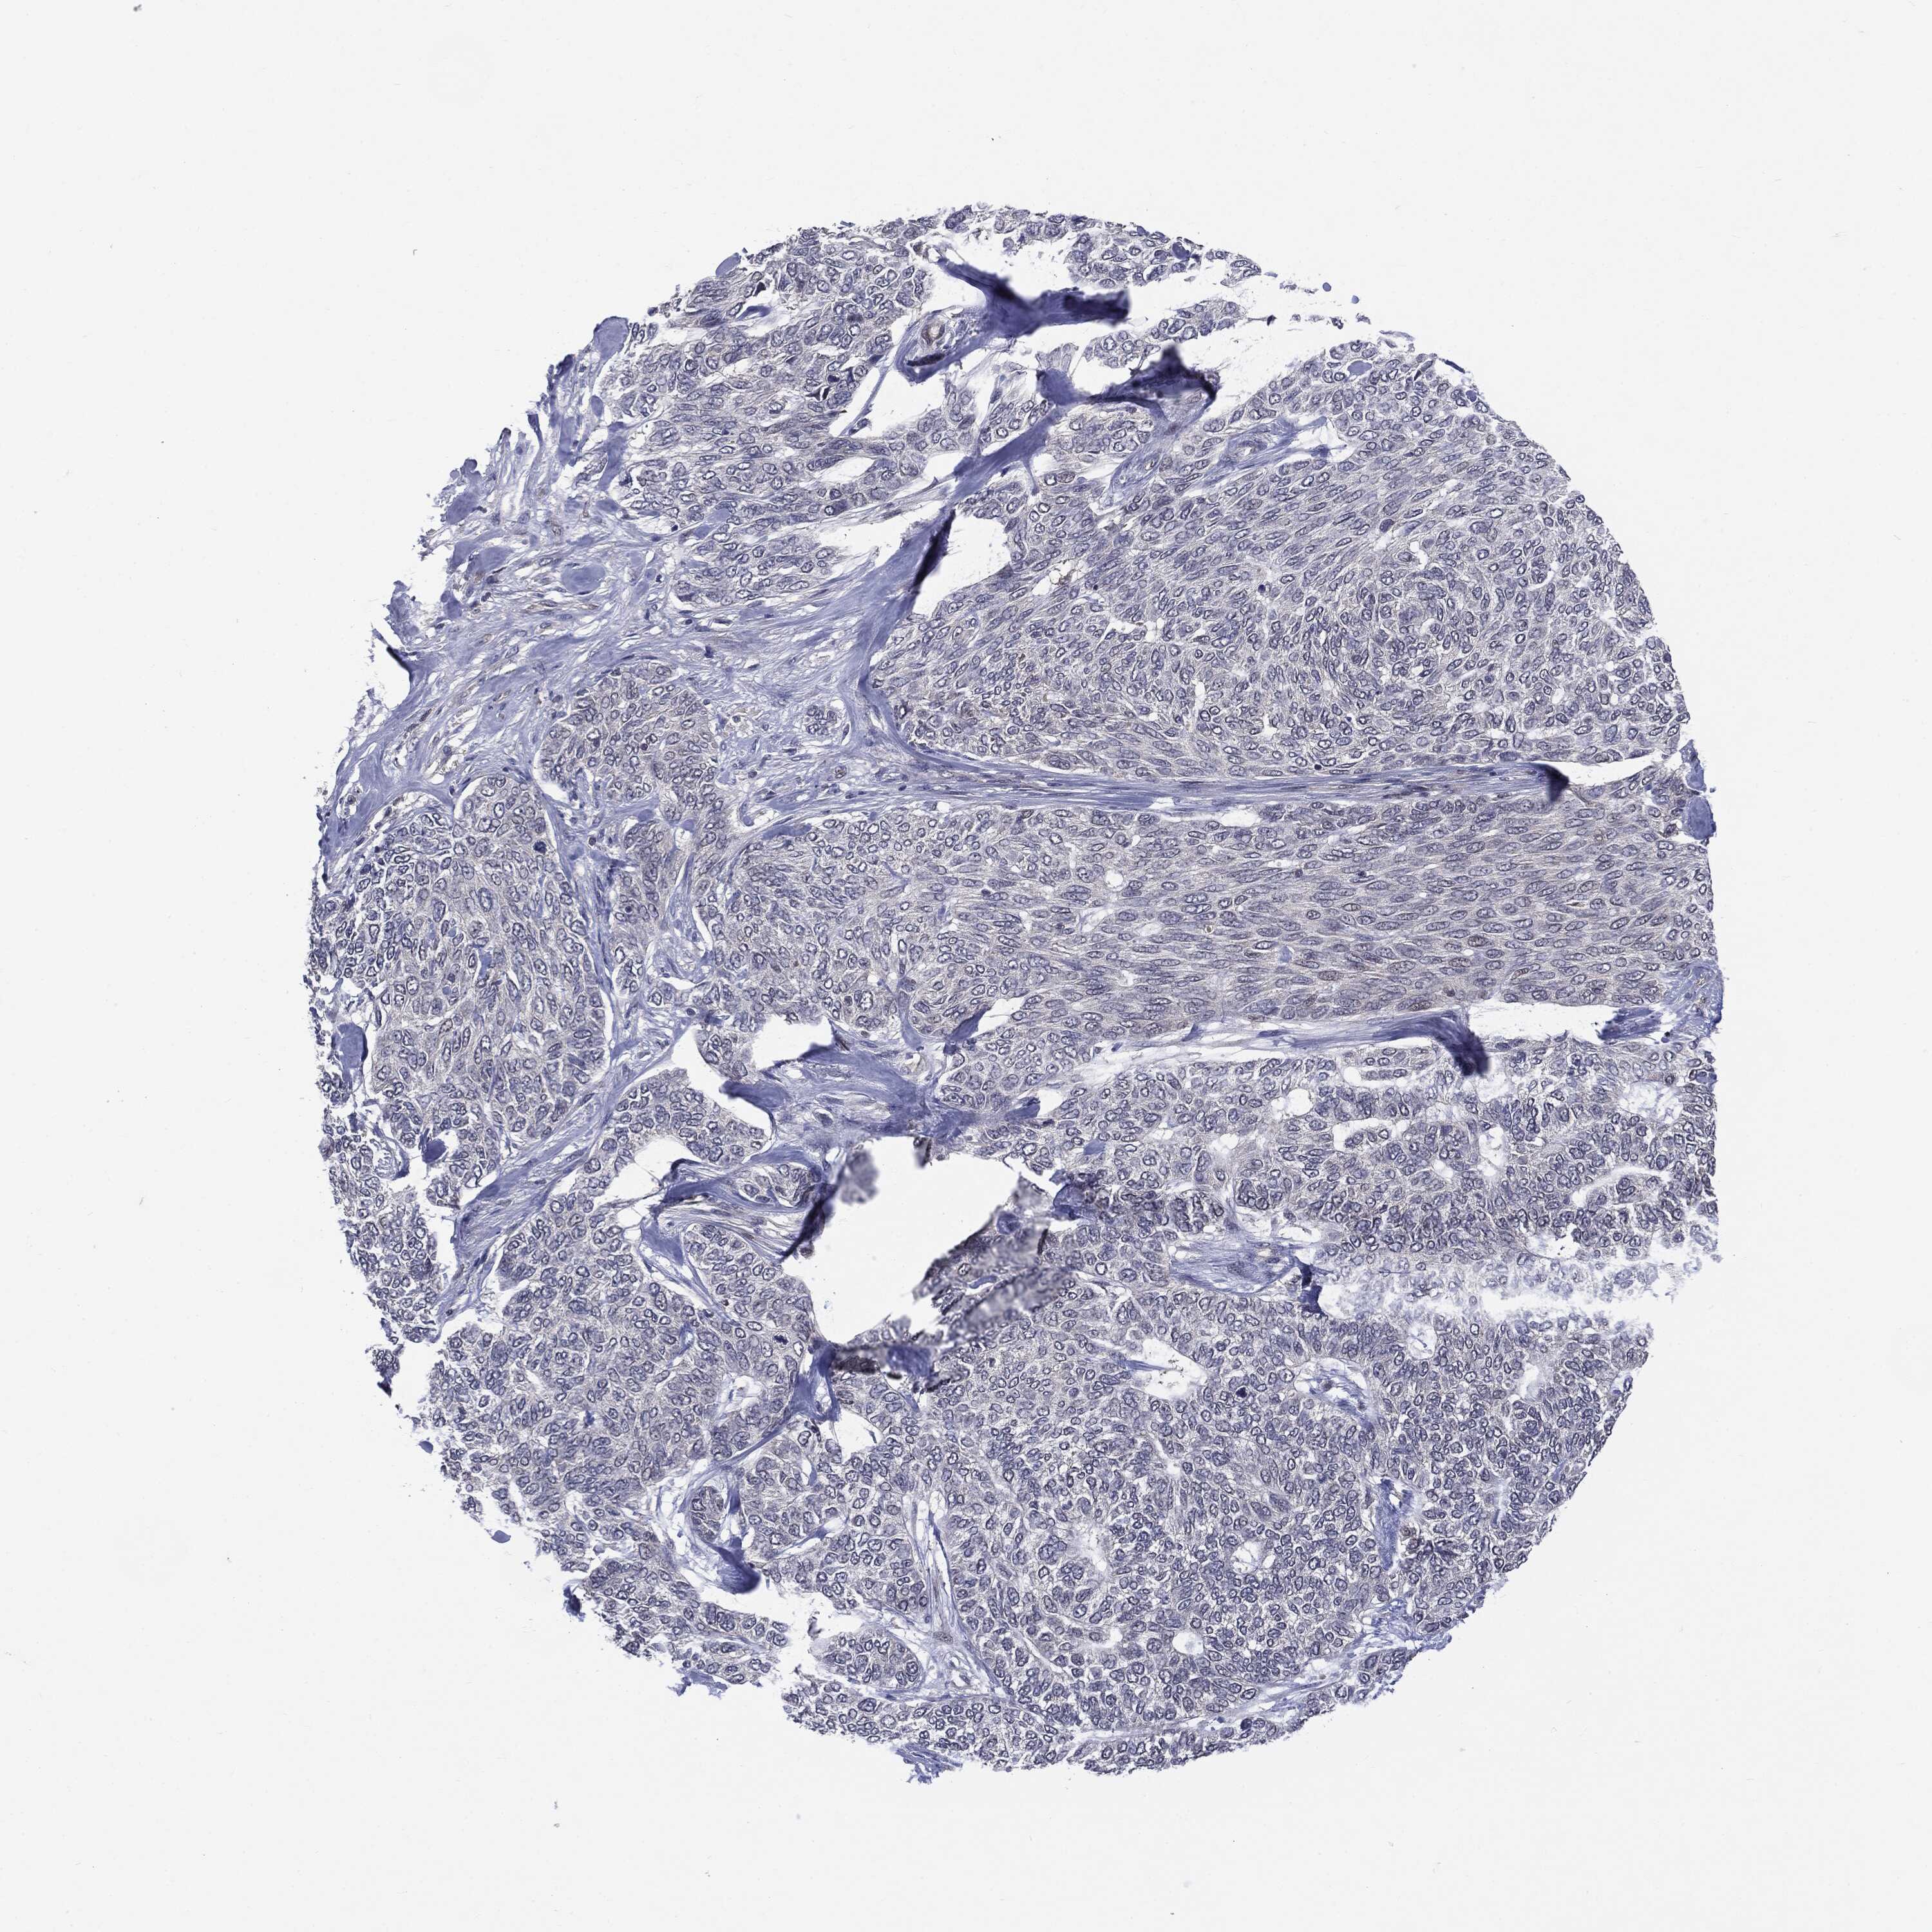

SKIN CANCER - Protein expressioni

A mouse-over function shows sample information and annotation data. Click on an image to view it in a full screen mode. Samples can be filtered based on level of antibody staining by selecting one or several of the following categories: high, medium, low and not detected. The assay and annotation is described here.

Antibody stainingi

Antibody staining in the annotated cell types in the current human tissue is reported as not detected, low, medium, or high, based on conventional immunohistochemistry profiling in selected tissues. This score is based on the combination of the staining intensity and fraction of stained cells.

Each image is clickable and will lead to virtual microscopy that enables deeper exploration of all samples and also displays staining intensity scores, fraction scores and subcellular localization as well as patient and tissue information for each sample.

CAB022068

Squamous cell carcinoma, NOS